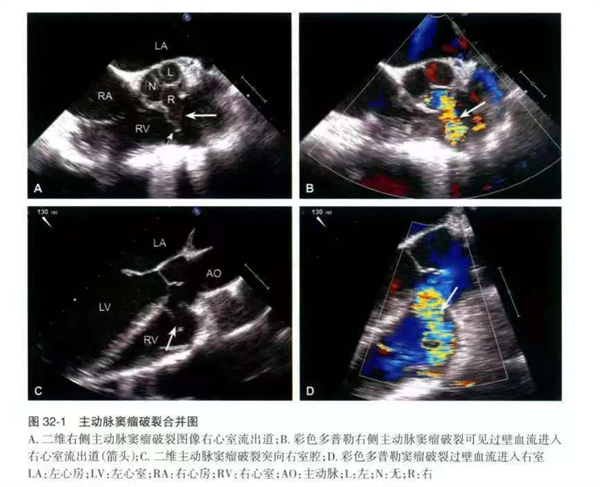

主动脉窦瘤(Sinus of Valsalva Aneurysm,简称 SOVA)是一种相对少见但极其危险的先天性心血管畸形。它发生在主动脉根部、紧贴心脏瓣膜(主动脉瓣)的三个“窦”状结构(冠状动脉从此发出)。简单来说,就是主动脉壁在心脏输出血液冲击最剧烈的根部位置,形成了一个异常薄弱、向外膨出的“瘤样”结构。

其凶险之处在于,它犹如一颗“不定时炸弹”:未破裂时,患者可能毫无症状,或仅有轻微不适(如心悸、胸闷),极易被忽视,常在体检或因其他疾病检查时偶然发现。然而,一旦破裂,便是灾难性的——由于该部位承受着心脏泵血产生的巨大压力(高压区),这个薄弱的瘤体随时可能破裂。破裂瞬间,主动脉内的血液会高速、大量喷射入邻近的心腔(最常见是右心房或右心室),导致心脏内压剧增、容量超负荷、全身有效循环血量骤降,患者可能突发剧烈胸痛、呼吸困难、大汗淋漓,甚至休克、意识丧失,死亡率极高。即使未在破裂即刻致命,但血液异常分流还会导致顽固性心力衰竭、严重的心律失常、感染性心内膜炎等致命并发症。而且,该疾病的诊断较为复杂,其症状易与其他常见心脏病(如冠心病、心肌病)混淆,确诊高度依赖超声心动图(尤其是经食道超声)、CT 血管成像(CTA)或心脏磁共振(CMR)等高级影像检查。